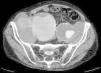

The patient was an 86-year-old man who was taking 2 medications for hypertension. He had a history of several months of low back pain that radiated to right thigh, for which symptomatic treatment provided partial relief. His rheumatologist had ordered thoracolumbar magnetic resonance imaging (MRI), but it was not performed because, prior to the scheduled date, the patient went to the emergency department with an increase in the intensity of the pain. Laboratory analyses showed a hemoglobin level of 8.4g/dL, lactate dehydrogenase of 318U/L, creatinine of 1.29mg/dL, C-reactive protein of 6.16mg/dL, erythrocyte sediment rate of 24mm/h and mild hypoproteinemia. There was no evidence of hemodynamic instability. He underwent abdominopelvic computed tomography (CT) with intravenous contrast, which revealed isolated bilateral iliac aneurysms>6cm (Fig. 1) with contained rupture of the aneurysm on the right (Fig. 2), which displaced the psoas muscle (Fig. 3) and perforated the ipsilateral iliac bone (Fig. 4). The patient underwent aortobifemoral bypass but, unfortunately, he died during the postoperative period.